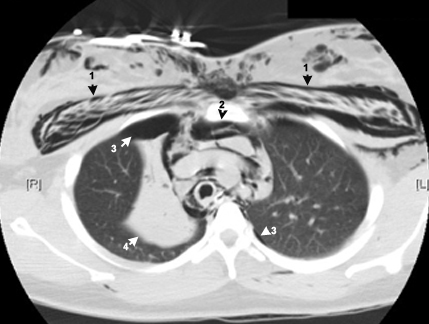

CT shows

1: Subcutaneous emphysema.

2: Pneumomediastinum.

3: Pneumothorax.

4: Collapsed right upper lobe.